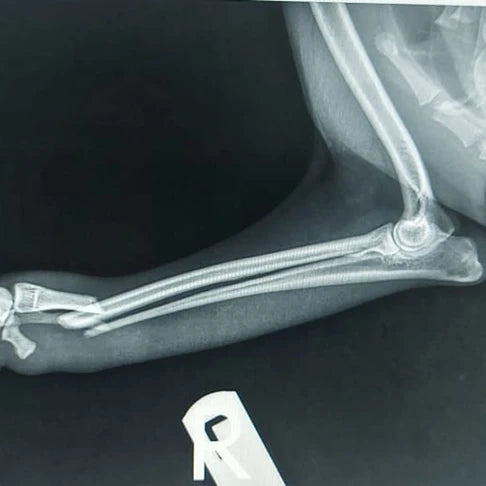

Coffee's Journey From Fractured Leg to Forever ...

Today, I am overjoyed to share the heartwarming conclusion of Coffee's journey—a tale of resilience, healing, and the incredible power of community support. A Tough Beginning Coffee's story began...